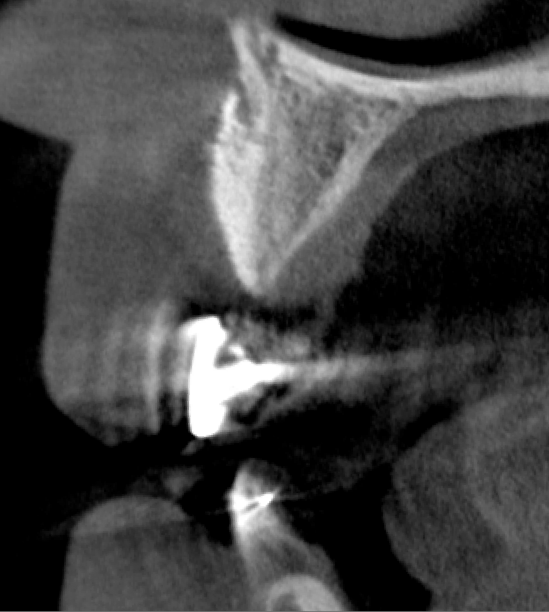

Tomographic images revealed a large tridimensional defect, with vertical and horizontal loss of bone extending to the apical third of teeth Nos. 6 and 8. Additionally, a buccal bone dehiscence was evident on tooth No. 5, and thin labial plates secondary to the orthodontic movement were present in several areas (Figure 3 and Figure 4).

After 3 months of post-orthodontic stabilization, a cone-beam computed tomography scan was taken to re-evaluate the results and plan the future treatment sequence. Tomographic images clearly showed vertical gains in alveolar height, including in the edentulous area corresponding to tooth No. 7 (Figure 10 through Figure 12). The apex of tooth No. 8 was forced-erupted beyond its socket and could be visibly located within the soft tissue.30,33

Because recession was already present on tooth No. 5, the scope of the SMART procedure was extended to horizontally augment adjacent areas that exhibited dehiscences and thin buccal plates (Figure 16). The augmented areas evident in Figure 16 (which can be compared to the preoperative imaging in Figure 4) were accomplished using two remote incisions. It must be emphasized, however, that this procedure may be technique sensitive, and predictable outcomes require training and experience. Unlike lateral subperiosteal techniques, the SMART method is based on the development of a laparoscopic tunnel from a remote incision to access the graft site. A subperiosteal pouch is subsequently created to confine the biomaterial particles (Figure 17 and Figure 18). This approach ensures that surgical trauma to the subperiosteum and the associated inflammatory reaction do not interfere with healing of the bone graft. Specially designed instruments are required to control the elevation of the periosteum, reach the graft site, and develop the subperiosteal pouch.